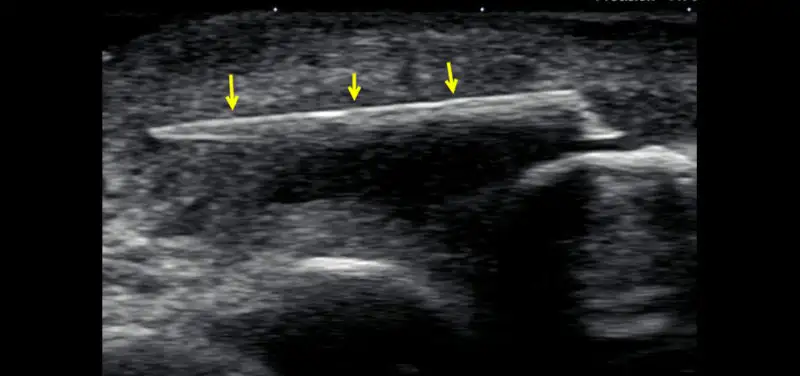

Image: Ultrasound image showing the bright linear structure of the retained wood fragment (arrows)

If x-rays fail to identify a retained soft tissue foreign body and one is suspected, ultrasound is the next imaging modality of choice. Most objects will be readily identified as a bright (echogenic) structure. Often the surrounding inflammatory changes are easily shown. Ultrasound can be used to help guide removal of the structure. Sometimes an MRI is performed to assess a suspected soft tissue infection and an unexpected foreign body is detected. Wood material is the most common and will often appear as a dark signal structure with surrounding soft tissue, bright signal inflammatory tissue or abscess.